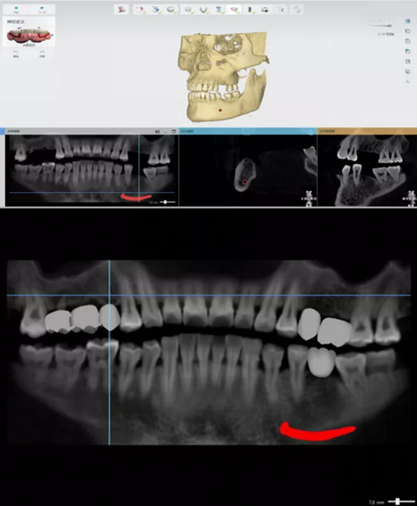

手術(shù)方案規(guī)劃

按咬合關(guān)系排列虛擬牙齒

手術(shù)規(guī)劃設(shè)計(jì)

繪制下頜神經(jīng)管

植體植入設(shè)計(jì)